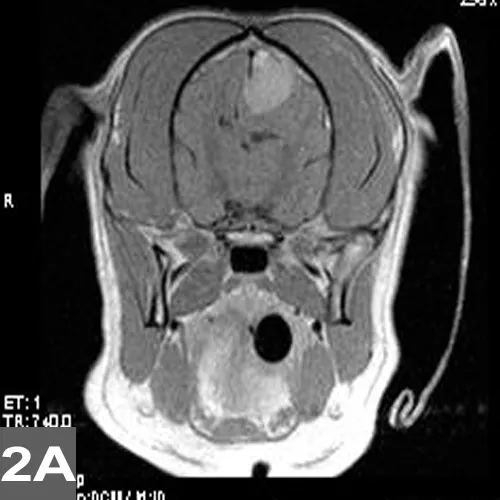

Initial diagnostics typically consist of emergency blood analysis (ie, glucose, electrolytes, blood gases, urea concentration, PCV/TS), but a more complete blood analysis (ie, CBC, chemistry panel, thyroid profile), urinalysis, additional screening tests (eg, thoracic radiography, ECG, abdominal radiography or ultrasonography), and blood pressure monitoring are often recommended. Other pertinent tests (eg, blood ammonia or bile acids, coagulation profile, insulin level, toxicologic and infectious disease diagnostics) depend on the suspected underlying disease and should be considered before pursuing advanced imaging (eg, MRI; Figure 2) and cerebrospinal fluid analysis.

Postgadolinium T1 axial (2A) and sagittal (2B) MRIs of a dog with a brain tumor